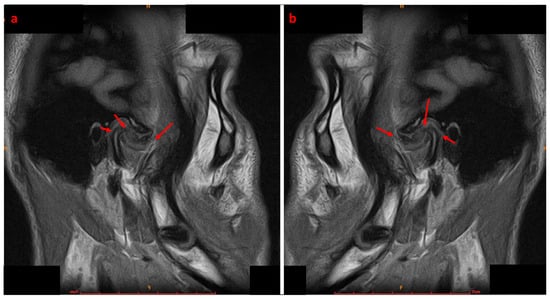

An Innovative Approach to Managing Temporomandibular Disorders Through the Combined Use of Two Oral Devices: A Case Report

by Antonio Spagnuolo, Roberta Iacono, Gian Mauro Liberatore and Carlo Di Paolo

Appl. Sci. 2026, 16(1), 273; https://doi.org/10.3390/app16010273 - 26 Dec 2025

Temporomandibular disorders (TMD) are increasingly prevalent in the adult population. Given the multifactorial and often chronic nature of TMD, the ideal therapeutic approach must be multimodal and personalized, with a preference for conservative treatments. However, standardized protocols combining occlusal devices and biobehavioral therapy for internal derangement (ID) are still lacking. Case Presentation: A 20-year-old male patient presented with bilateral anteromedial reducible disc displacement, with intermittent locking on the right. He reported joint noises, difficulty chewing, and occasional painful mouth opening. A comprehensive diagnostic workup, including clinical, functional, and radiographic evaluations, was performed. The patient underwent a biobehavioral gnathological therapy involving two oral devices: RA.DI.CA. and By-Te ® Reali. The protocol included personalized exercises, patient education, and behavioural counselling. Results. The patient achieved full remission of pain, disappearance of joint noises, and restoration of mandibular function, without dental movement. Pre- and post-treatment MRI and condylography confirmed improved condyle-disc relationships, increased intra-articular space, and better symmetry of movements, particularly on the right. Conclusion. The combined use of RA.DI.CA. and by-Te ® Reali devices, supported by a personalized functional programme, appears effective in managing TMD with ID. Further studies on larger populations are needed to confirm the efficacy and safety of this protocol. Full article